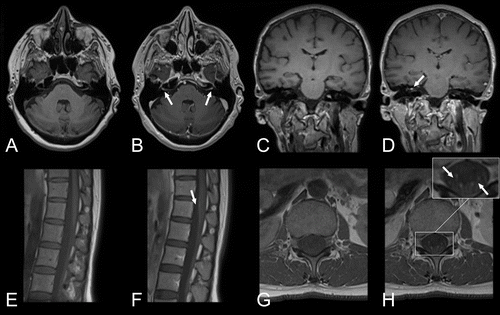

La neuroradiologie est une sous-spécialité de la radiologie, spécialisée dans l'imagerie diagnostique du cerveau, de la colonne vertébrale, de la tête et du cou.

Les neuroradiologues ont une formation en radiologie diagnostique pour étudier diverses maladies telles que les accidents vasculaires cérébraux, les maladies démyélinisantes, les maladies neurodégénératives, les tumeurs cérébrales, les cancers de la tête et du cou, les maladies neurovasculaires, les traumatismes, les douleurs dorsales et d'autres maladies neurologiques.

Les principales modalités d'imagerie sont la tomodensitométrie (Scanner) et l'imagerie par résonance magnétique (IRM).